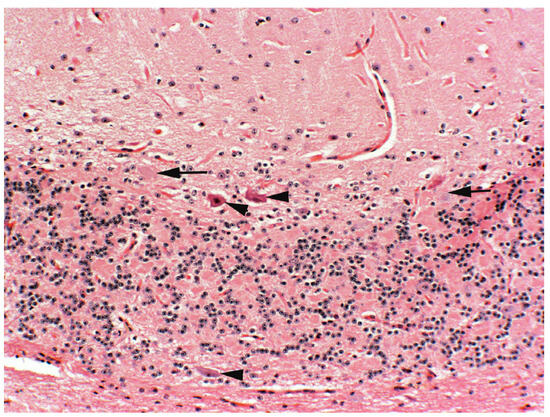

2. Locoweeds

- Stegelmeier, B.L.; James, L.F.; Panter, K.E.; Ralphs, M.H.; Gardner, D.R. The pathogenesis and toxicokinetics of locoweed (Astragalus and Oxytropis spp.) poisoning in livestock. J. Nat. Toxins 1999, 8, 35–45. [Google Scholar] [PubMed]

- Stegelmeier, B.L.; James, L.F.; Panter, K.E.; Molyneux, R.J.; Gardner, D.R.; Lee, S.T.; Ralphs, M.H.; Pfister, J.A. The Clinical and Morphological Changes of Intermittent Locoweed (Oxytropis sericea) Poisoning in Sheep. In Poisonous Plants and Related Toxins; Acamovic, T., Stewart, C.S., Pennycott, T.W., Eds.; CABI Publishing: Wallingford, UK, 2004; pp. 431–435. [Google Scholar]

- Stegelmeier, B.L.; James, L.F.; Panter, K.E.; Molyneux, R.J.; Gardner, D.R.; Lee, S.T.; Ralphs, M.H.; Pfister, J.A. Dose response of sheep poisoned with locoweed (Oxytropis sericea). J. Vet. Diagn. Investig. 1999, 11, 448–456. [Google Scholar] [CrossRef]